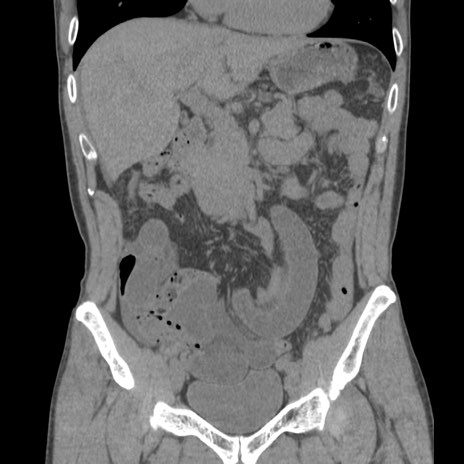

症例56 CT(冠状断像)

脂肪ウインドウ